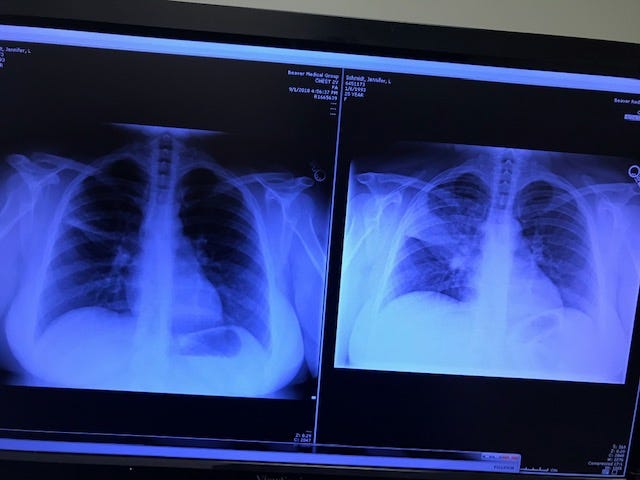

I want to interrupt this story to clarify what pneumonia is, it is an infection that causes the air sacs in one or both lungs to fill with fluid or pus. In my case, it was my left lung. I had 18% non-functioning lung at the height of my sickness. It causes you to cough with phlegm, feel exhausted and have difficulty breathing.

I slept for several hours and then had a friend take me to Urgent Care later that evening. The doctor knew what was wrong with me right away. He had a chest xray done and sure enough, he found the pneumonia. Luckily, he felt I could possibly be treated as an outpatient, so I didn’t have to be admitted to the hospital. But in the end, it still took about a week for me to be able to fully function. The first couple days of the illness walking the twenty steps to the bathroom was laborious. I lost about 25 lbs. over almost two weeks. I wasn’t eating and I wasn’t doing anything more than laying around and sleeping, but my heart was working very hard because I wasn’t breathing well. The graph, above, from my Fitbit shows how my resting heart rate spiked to 80 BPM at the height of the illness.